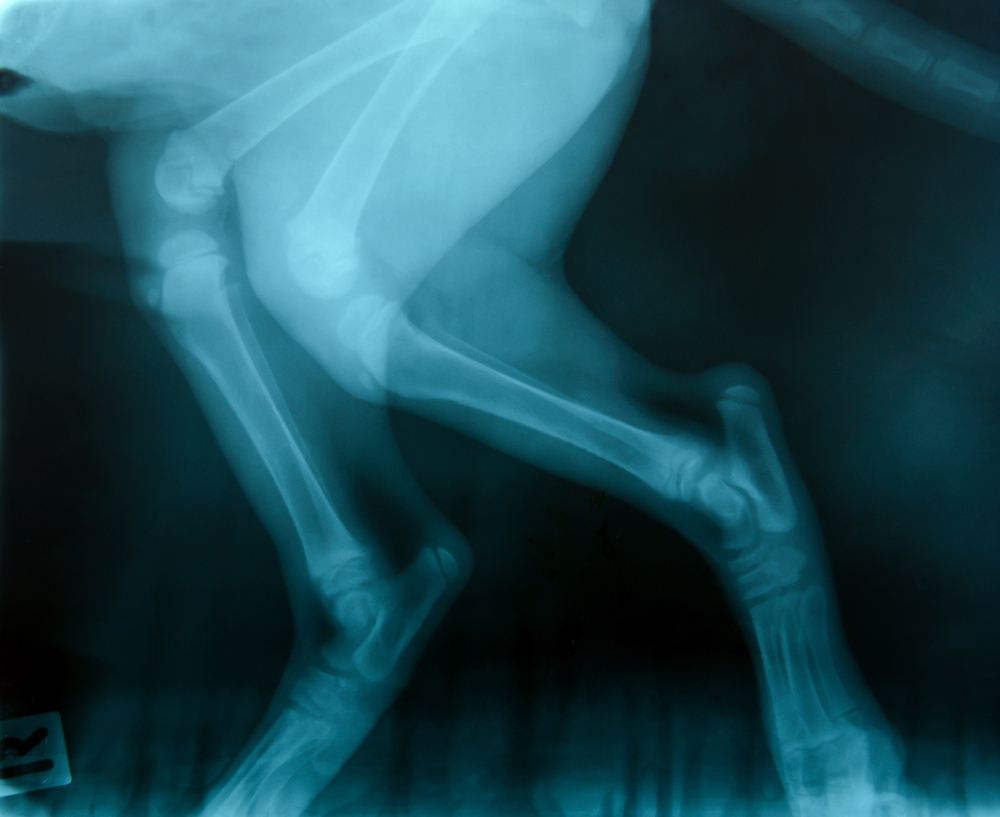

Radiografías

Disponemos de equipo de radiografía digital móvil para detectar lesiones óseas, cojeras u otros problemas estructurales. Este servicio mejora la precisión en el diagnóstico y nos permite tomar decisiones clínicas más acertadas en el lugar y momento adecuados.